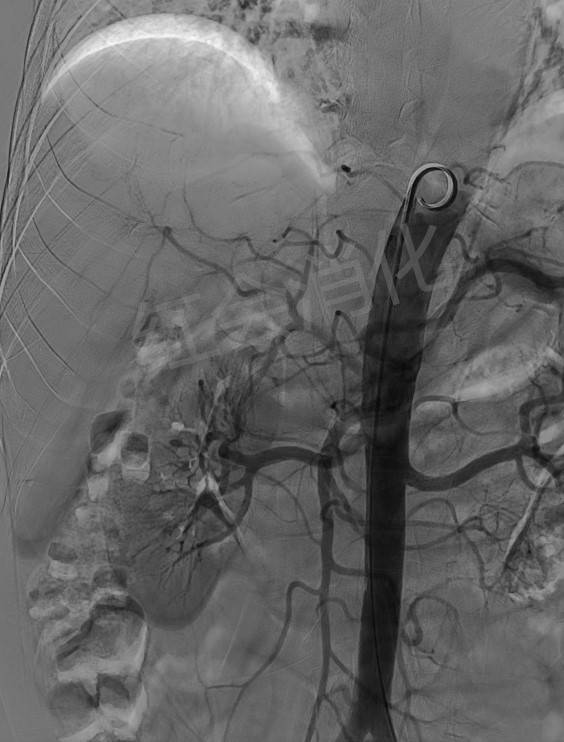

栓塞前造影

文章图片

超选后造影

栓塞后造影

入院后 , 张大爷仍有腹痛症状存在 , 接诊医生余天垒为张大爷行TACE术治疗 。 经过精心、细致的介入术前准备 , 余天垒医师经股动脉建立到肝动脉的血管路径 , 透视引导下注射造影剂 , 准备判断肿瘤供血动脉来源、数量、直径 。 由于患者的肿瘤巨大 , 四周缠绕密布着血管 , 精准地找到肿瘤供血血管后 , 注射化疗药物 , 直至药物抵达供血动脉最末端血管 , 待整条通道被药物填满 , 致密栓塞后彻底阻断肿瘤供血来源 。 余天垒医师解释道:TACE术形象的讲就是通过掐断肿瘤供血动脉 , 让肿瘤“饿”死 。 栓塞后再次造影显示 , 张大爷巨块型肿瘤的所有血管已完全阻断 。